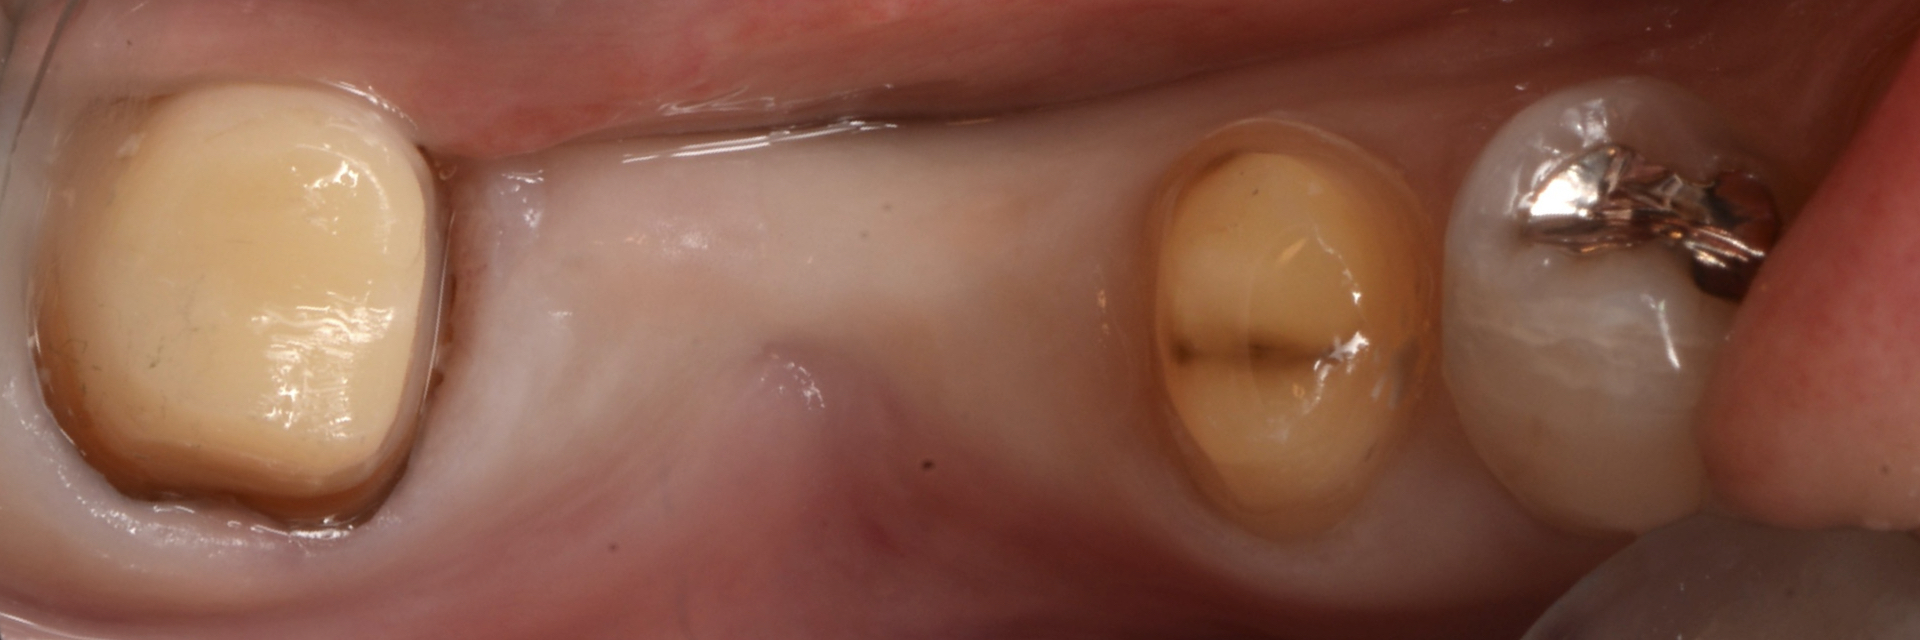

- 治療前

| 主訴 | ブリッジの部分をインプラントに変えたい |

| 治療内容 | 欠損部分にインプラントを埋入。インテグレーション後、プロビジョナルレストレーションを介して、最終補綴物を装着。 |

| 患者様の年齢 | 60代 |

| 患者様の性別 | 女性 |

| 治療期間 | 5ヶ月 |

| 治療費 | 50万円前後 |

| 治療で得られるメリット | 周囲の歯が守られる。 審美的 フロスが入る 単独の歯になる |

| 治療する際に起こる リスク・副作用 |

神経の損傷のリスク セラミックのチップ インプラント周囲炎 |